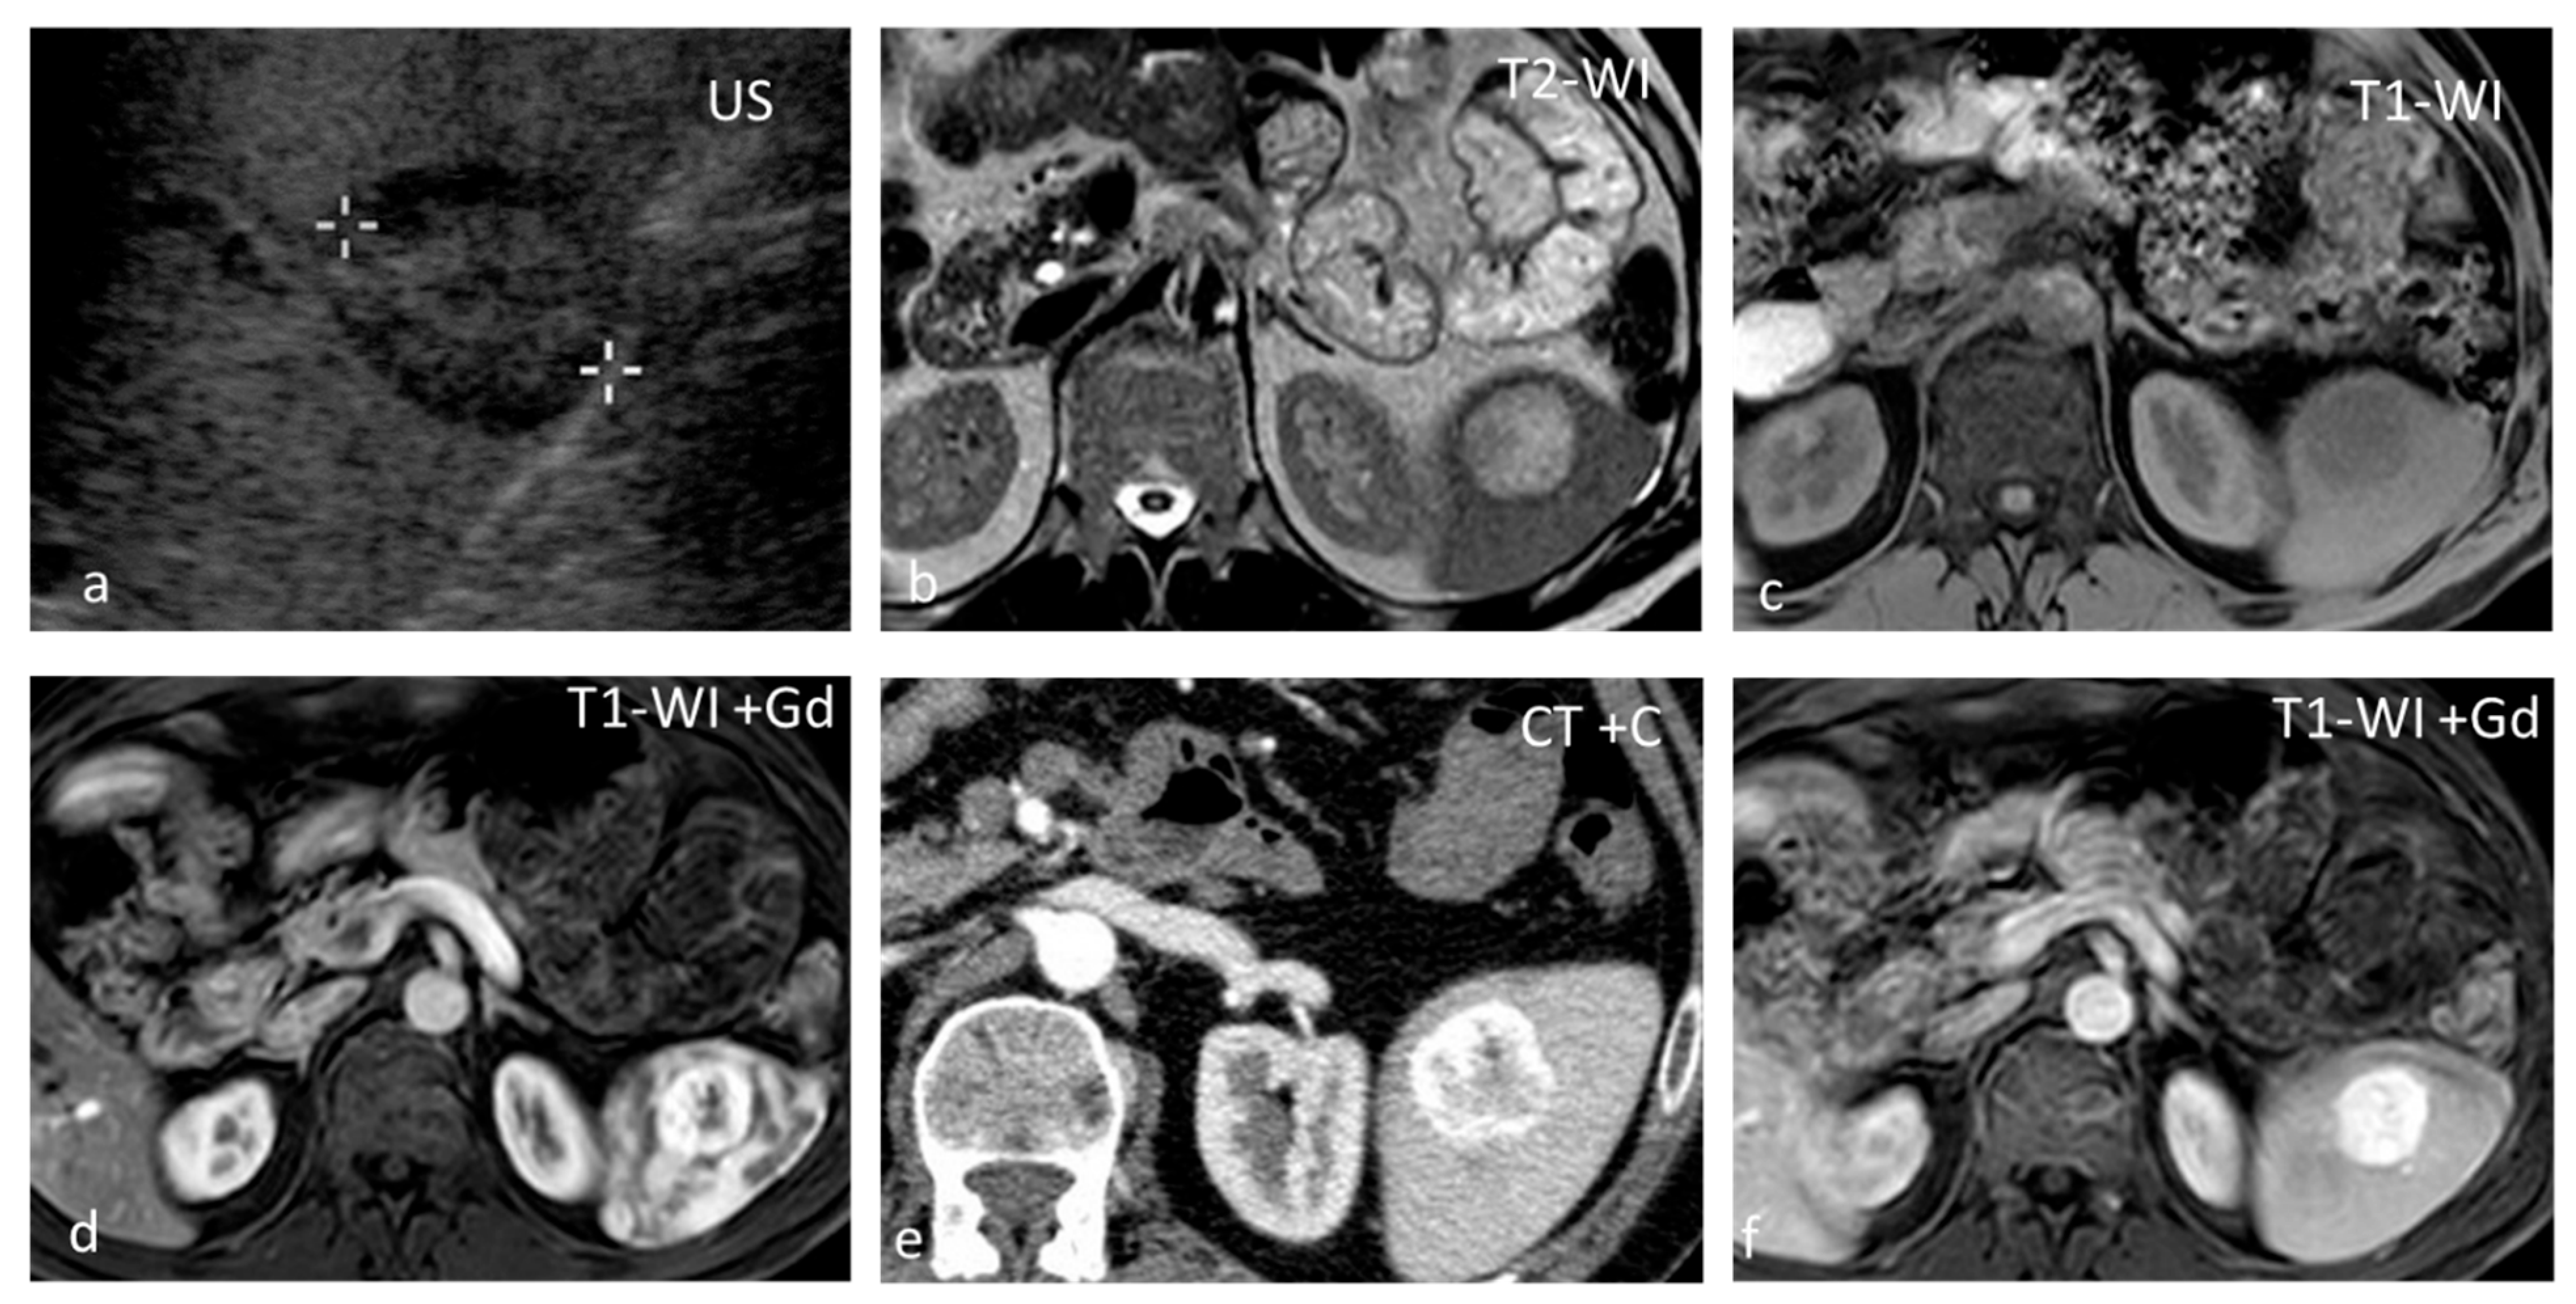

Sarcoidosis is a multisystem disease characterized by the presence of non-caseating granulomas. One-third of patients presenting with splenic sarcoidosis findings have normal chest radiography [18]. Splenic involvement has been reported in about 40% of cases of multisystem sarcoidosis, but isolated sarcoidosis of the spleen is extremely rare [19]. It may present either as splenomegaly or with multiple nodules, whereas a solitary splenic lesion is very rare. Patients with diffuse splenic granulomas have a worse prognosis in terms of persistent chronic sarcoidosis than patients without splenic involvement or patients with limited splenic disease [20]. Nodules appear hypodense on CT and have low SI both on T1-WI and T2-WI, with minimal delayed enhancement [21] (Figure 2). Nodules are best seen on T2-WI with fat saturation and on early gadolinium-enhanced T1–WI. MRI is said to be able to monitor disease activity, as during active inflammation, nodules demonstrate T2-WI hyperintensity due to edema and high vascular permeability, as well as restricted diffusion [22]. The main differential diagnosis includes infections, especially tuberculosis, and malignancies, especially lymphoma. The final diagnosis is based on three main criteria: a compatible presentation, the evidence of non-caseating granulomas on histological examination, and the exclusion of any alternative diagnosis [23].

Figure 2.

Sarcoidosis. US shows multiple hypoechoic nodules (a). The nodules appear slightly hypointense on T2 WI (b) and show mild delayed enhancement (c,d).

Hemangioma, although rare, is the most common splenic neoplasm and is found in up to 14% of patients at autopsy. It is formed by a proliferation of vascular channels, lined by a single layer of epithelium, and filled with blood. Hemangiomas are usually asymptomatic, solitary, or multiple. The natural course of hemangiomas is slow growth, and symptoms or complications, when present, occur late. Splenic hemangiomas may occur as part of generalized angiomatosis, as seen in Klippel–Trenaunay syndrome. Complications include rupture, hypersplenism, and malignant degeneration. Kasabach–Merritt syndrome, which involves the triad of anemia, thrombocytopenia, and coagulopathy, has been reported in patients with large hemangiomas [32]. Hemangiomas are round-shaped lesions with well-defined margins and a diameter <2 cm. Calcifications and cystic changes may be seen in up to 30% of cases. On US, hemangiomas have a variable appearance, being most commonly hyperechoic [32]. They appear hypoattenuating on non-contrast CT, hypo- to isointense on T1-WI, and hyperintense on T2-WI (Figure 6). Contrast enhancement can be immediate, homogeneous, and persistent or present as early peripheral enhancement with either uniform delayed enhancement or with fill-in and delayed enhancement of a central fibrous scar. Spontaneous rupture has been reported to occur in 25% of splenic hemangiomas, and treatment in such cases most often consists of splenectomy. In a study including 32 patients with splenic hemangiomas,11 of the patients had splenic lesions characterized as such based on their typical imaging findings on CT and US alone, while all were managed successfully with observation [33].

Figure 6.

Hemangioma. A well-defined isoechoic splenic lesion with a hypoechoic rim on US (a). The lesion appears hyperintense on T2-WI with a thin hypointense rim (b) and hypointense on T1-WI (c), demonstrating strong peripheral enhancement in the early phases post intravenous contrast administration both at MRI (d) and CT (e), and homogeneous delayed enhancement (f).